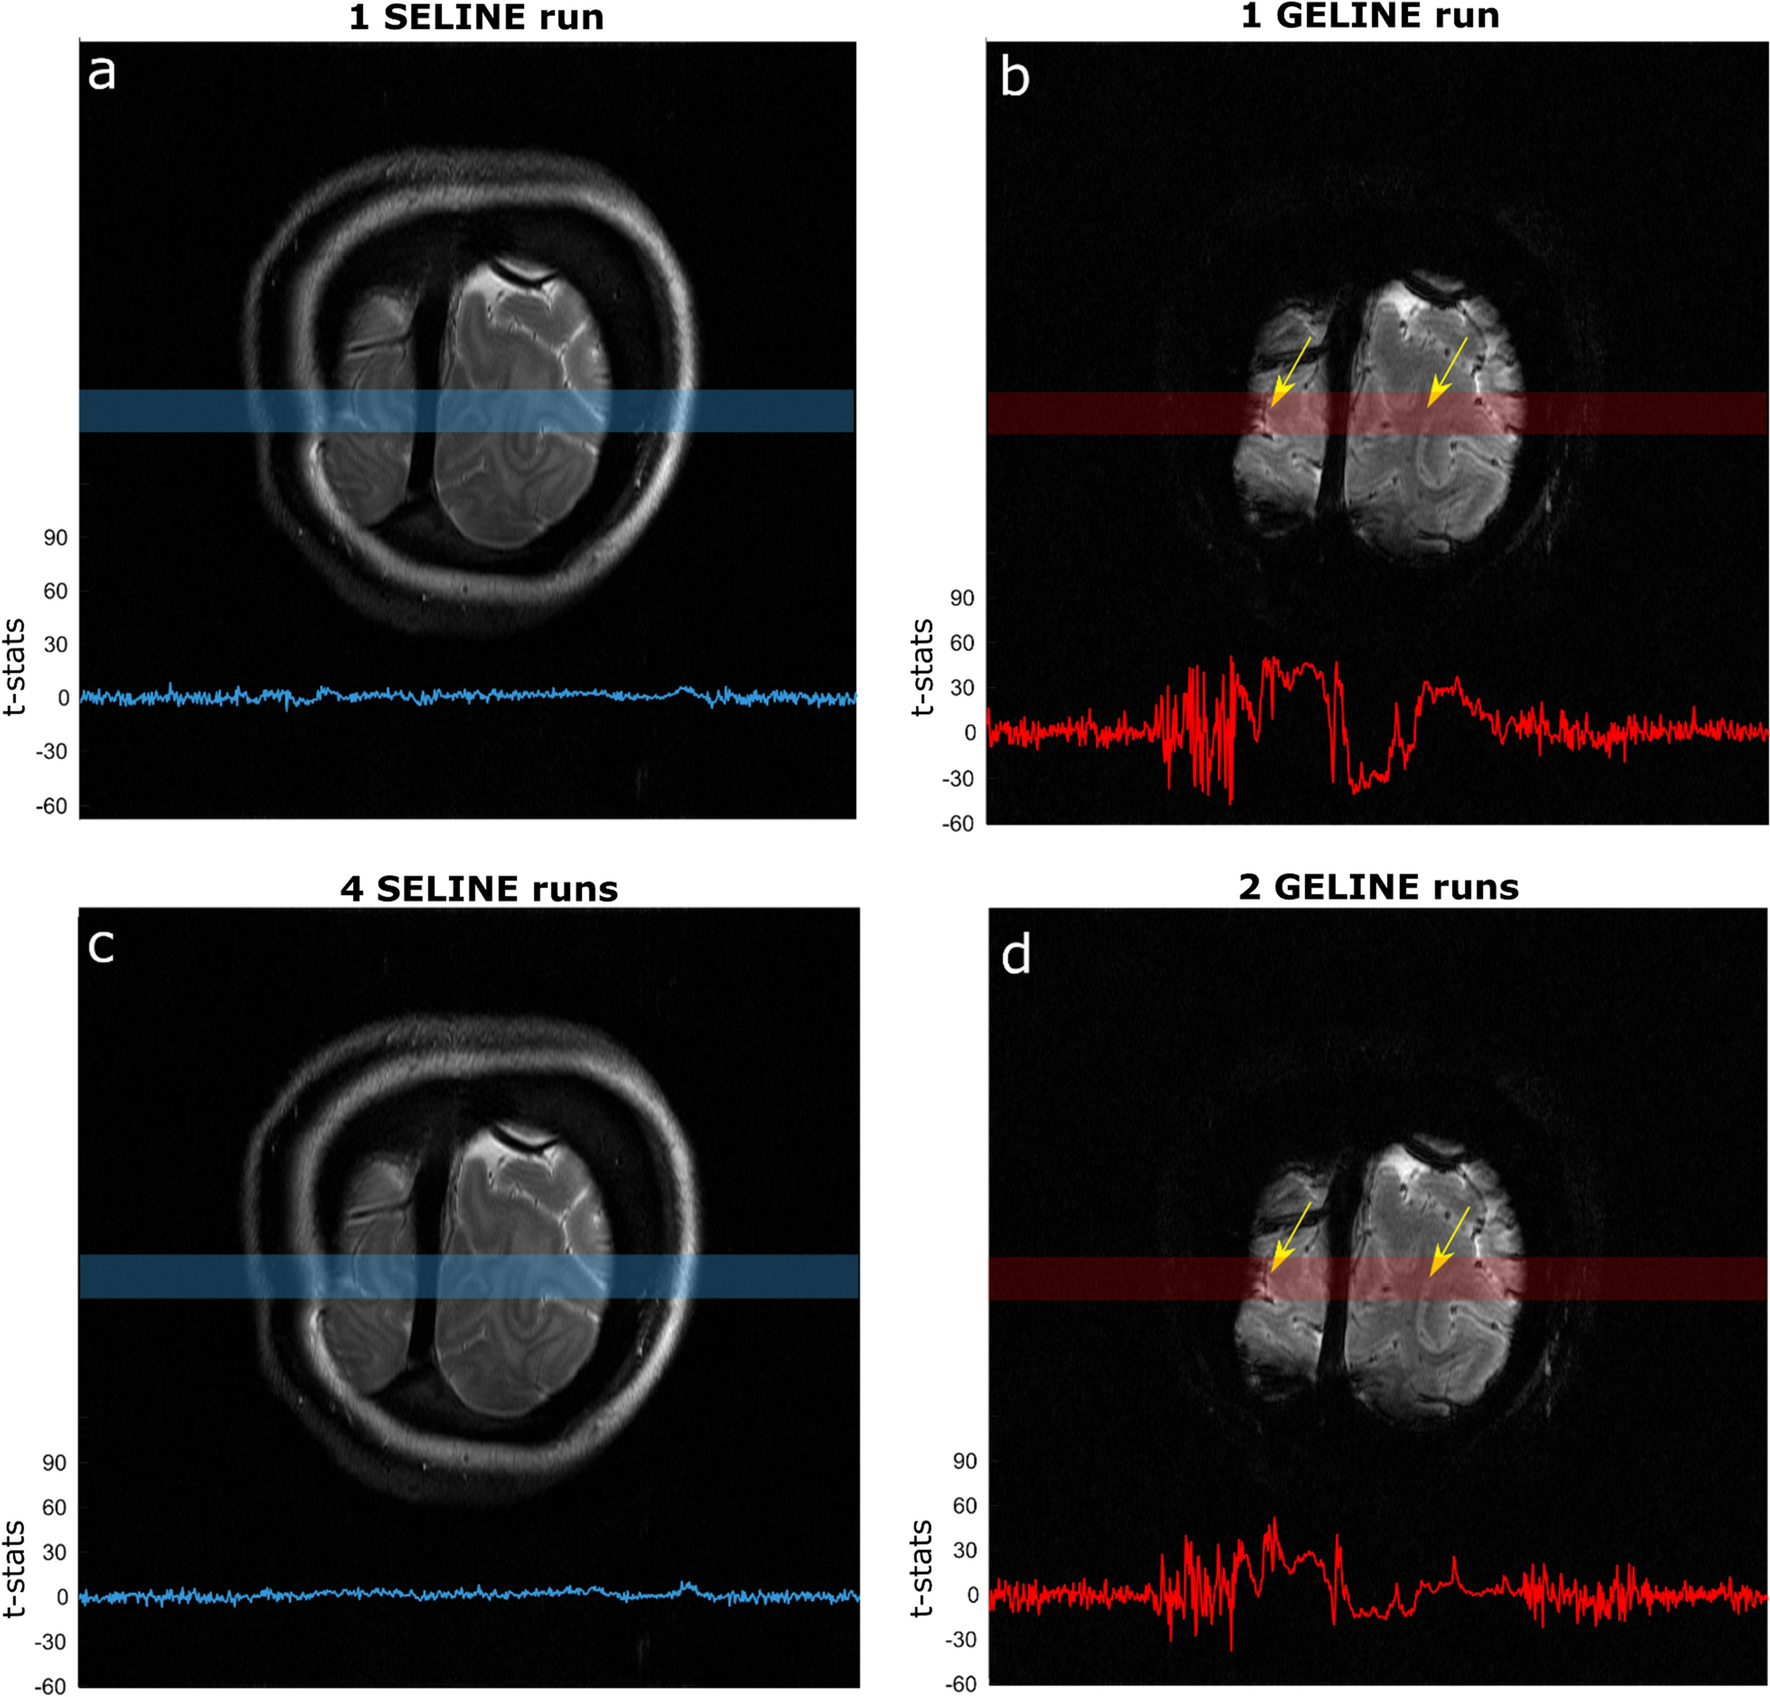

As might be expected from the lower tSNR values, SELINE acquisitions also yielded low functional responses. Figure 4 shows the t-stats values obtained from the GLM of 1 run of SELINE (a) and GELINE (b) and for the average of, respectively, 4 and 2 runs (c and d), overlaid on the acquired slices for SE and GE. While one run of GELINE activation is visible, with relatively high t-stats in the gray matter areas of the line (yellow arrows), even the average of 4 runs of SELINE does not lead to easily detectable responses. Only small responses are visible in the gray matter areas.

Fig. 4

a t-stats for 1 SELINE acquisition, b 1 GELINE acquisition, c 4 runs average SELINE acquisition and d 2 runs average GELINE acquisition, overlaid on the acquired slices, for the same representative participant. The light blue and red boxes indicate where the line was positioned, and the yellow arrows highlight gray matter regions

On average, across subjects, we found that 1 run of GELINE furnished 3.9 times higher mean value of t-stats along the line, compared to 1 run of SELINE.